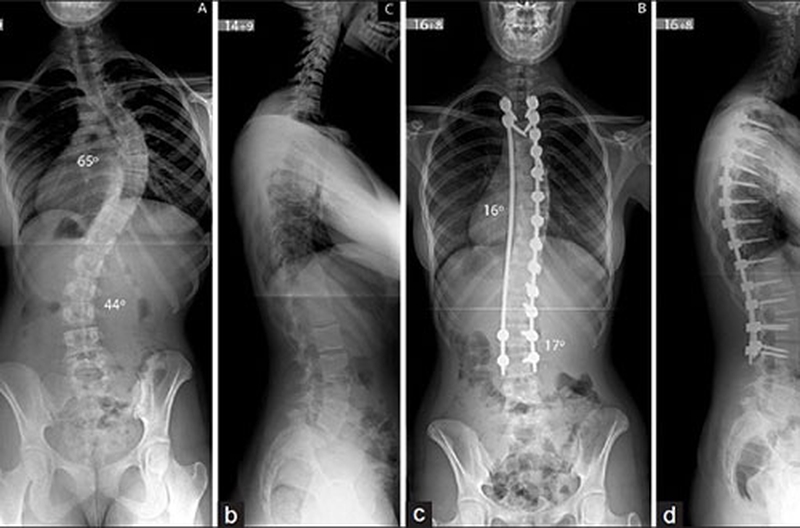

Ta có thể nhận biết bệnh vẹo cột sống lưng thông qua các triệu chứng ở bên ngoài, tuy nhiên bác sĩ sẽ thực hiện một số tiếp cận lâm sàng như chụp X - Quang KTS và MRI để xác định chính xác tình trạng bệnh.

Phẫu thuật vẹo cột sống sẽ phụ thuộc vào thời điểm khởi phát của bệnh và mức độ nặng, sự biến dạng của cột sống và ở trong một số trường hợp, việc phẫu thuật sẽ phụ thuộc vào vị trí của biến dạng. Bác sĩ sẽ có các phương pháp điều trị khác nhau với từng trường hợp trẻ bị vẹo cột sống, cụ thể:

• Độ cong vẹo trên 45º: Có thể sẽ cần can thiệp phẫu thuật.

Phẫu thuật là biện pháp có thể khắc phục tốt các cột sống bị sai lệch nhưng so với người lớn, phẫu thuật ở trẻ em phức tạp hơn bởi sẽ thường gặp các rủi ro, một vài các biến chứng có thể gặp sau phẫu thuật như hôn mê, sốc thuốc và tổn thương thần kinh,... Ngoài ra, chi phí cho các ca phẫu thuật vẹo cột sống ở trẻ thường cao hơn, gây khó khăn cho nhiều gia đình.